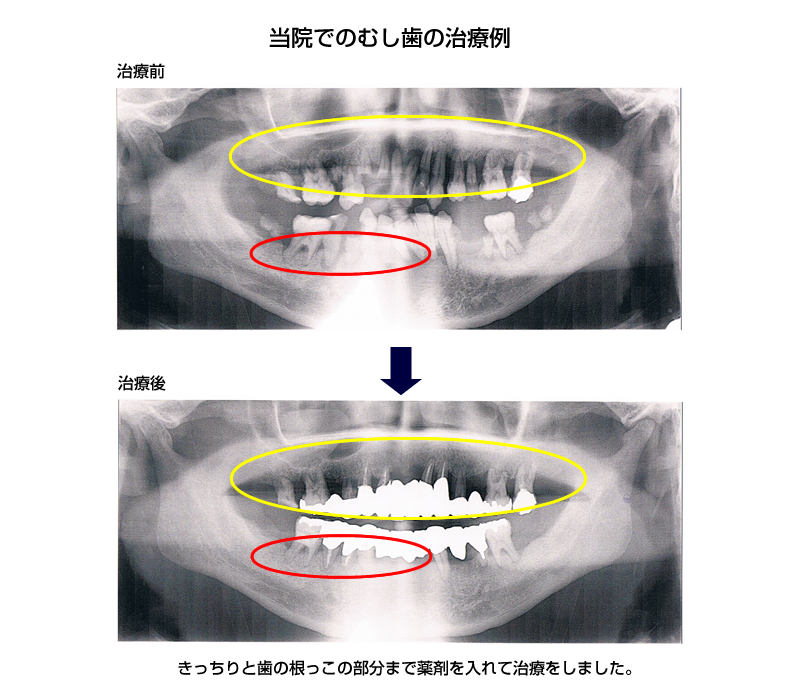

根管治療

根管治療とは、歯の根っこ(根管)の中の細菌に感染した部分を除去し、修復する治療です。

根管内を十分に殺菌・洗浄したのち、再び細菌感染を起こさないように根管に薬剤を充填します。

根管は人それぞれ形態異なり、根の先が分かれていたりと非常に複雑な形状をしています。ですので、根管治療には高い精密さが求められます。

根管治療を行うことで歯を抜かずになるべく自分の歯を残すことが可能になります。

↑